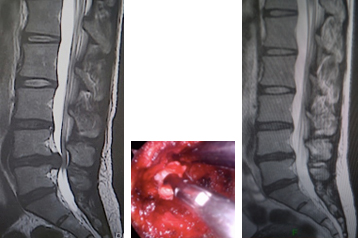

(左)術前MRI 第4/5腰椎に椎間板ヘルニアを認めます。(中)内視鏡下(MED)にヘルニアを摘出しました。(右)術後MRI 第4/5腰椎の椎間板ヘルニアが消失しています。